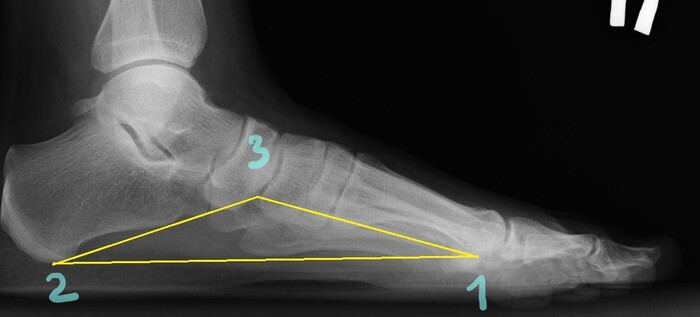

Как определить степень плоскостопия по R снимкам

Для определения наличия плоскостопия и его степени выполняют рентгенографию

стоп с нагрузкой по методике Богданова И.О.

Производят снимки в условиях естественной статической нагрузки, в

боковой проекции с захватом 4-5 см голени. На рентгенограмме измеряют высоту

продольного свода стопы и угол его наклона  Для этого

соединяют горизонтальной линией подошвенную поверхность головки I плюсневой

кости(точка 1) и нижнюю точку бугра пяточной кости(точка 2). Концы этой линии соединяют с

наиболее низкой точкой клино-ладьевидного сустава(точка 3).

Из данной точки(3) опускается перпендикуляр на проведенную горизонтальную

линию. Высота этого перпендикуляра - высота продольного свода стопы. Угол между

косыми линиями у вершины перпендикуляра - угол свода стопы. В норме высота

равна 36-39 мм, угол - 125-130 градусов.

Степени плоскостопия.

Заветная категория годности для призывников-В(ограниченно годен к военной службе)-присваивается при 3(третьей) степени плоскостопия то есть от 156 град.